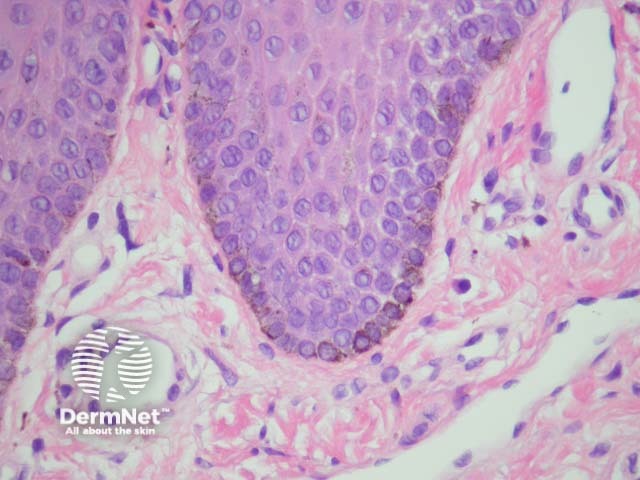

An occasional feature of lentigo simplex is isolated junctional nests of melanocytes. A lentiginous naevus (also called naevoid lentigo or ‘jentigo’) has few junctional nests and lentiginous melanocytic hyperplasia at the periphery (figure 6). A continuum may exist whereby lentigo simplex can evolve to form junctional then compound and finally intradermal naevi.

Figure 6